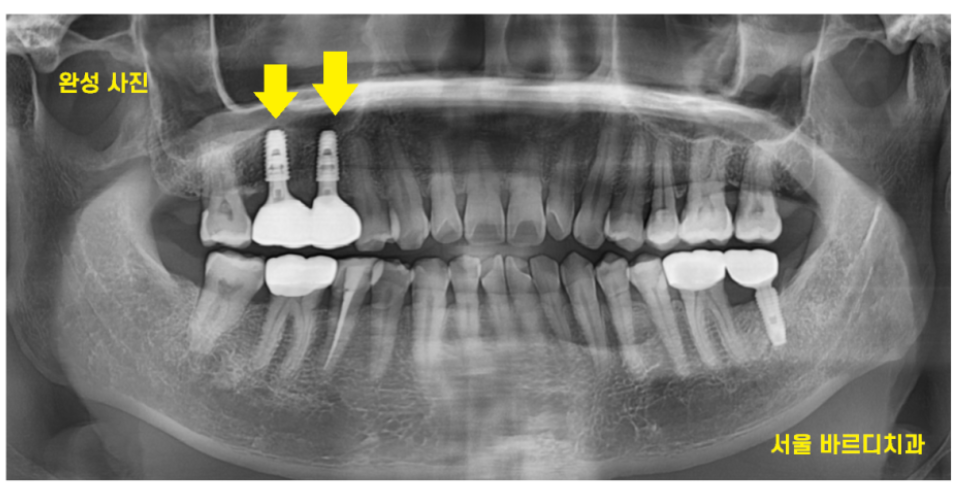

두번째로 정기검진을 자주 오시는 겁니다 .

24.01.02

잇몸뼈가 얼마나 내려갔는지

임플란트에 문제가 없는지 확인하기 위해서입니다.

불편한게 없으셔도 풍산동 치과를 주기적으로 오셔야

임플란트 음식물 끼임은 없는지

확인도 하고

보철물을 수정한다거나 해결해드릴 수 있으니까요